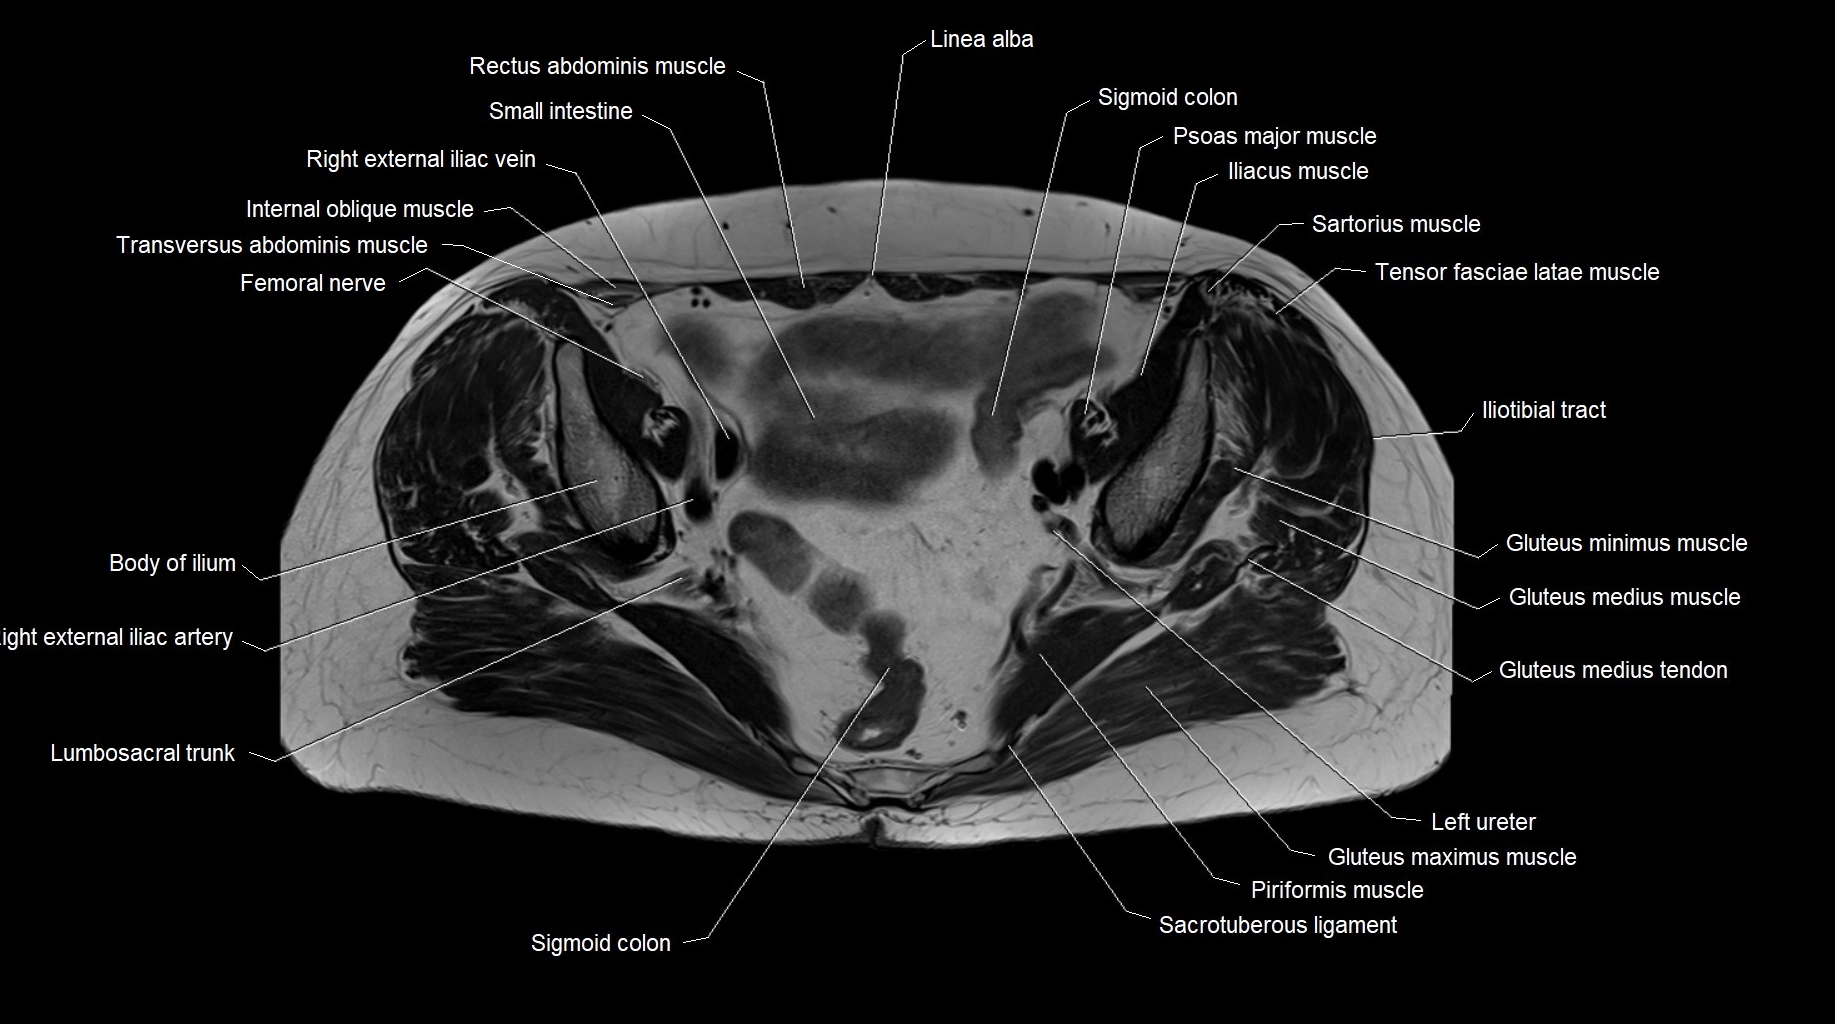

MRI images